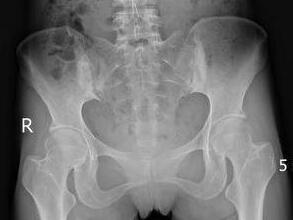

体格检查:脊柱生理弯曲度消失,颈部活动受限,前仰30°,后仰15°;腰椎活动受限,前屈70°,后屈0°;右髋关节压痛(+),右膝呈伸–4度畸形,左膝屈90度,伸–10度;骨盆挤压分离试验(+),双"4"字测试查体欠合作;枕墙距16cm,胸廓扩张度1.0cm。

辅助检查:CPR:33.08mg/l,RF:12.30Iu/ml,ESR:55.0mm/h;HLA-B27(+)X光片示:椎体向右侧弯曲,间隙模糊狭窄,骶髂关节炎。

(图:患者骶髂关节X线片)